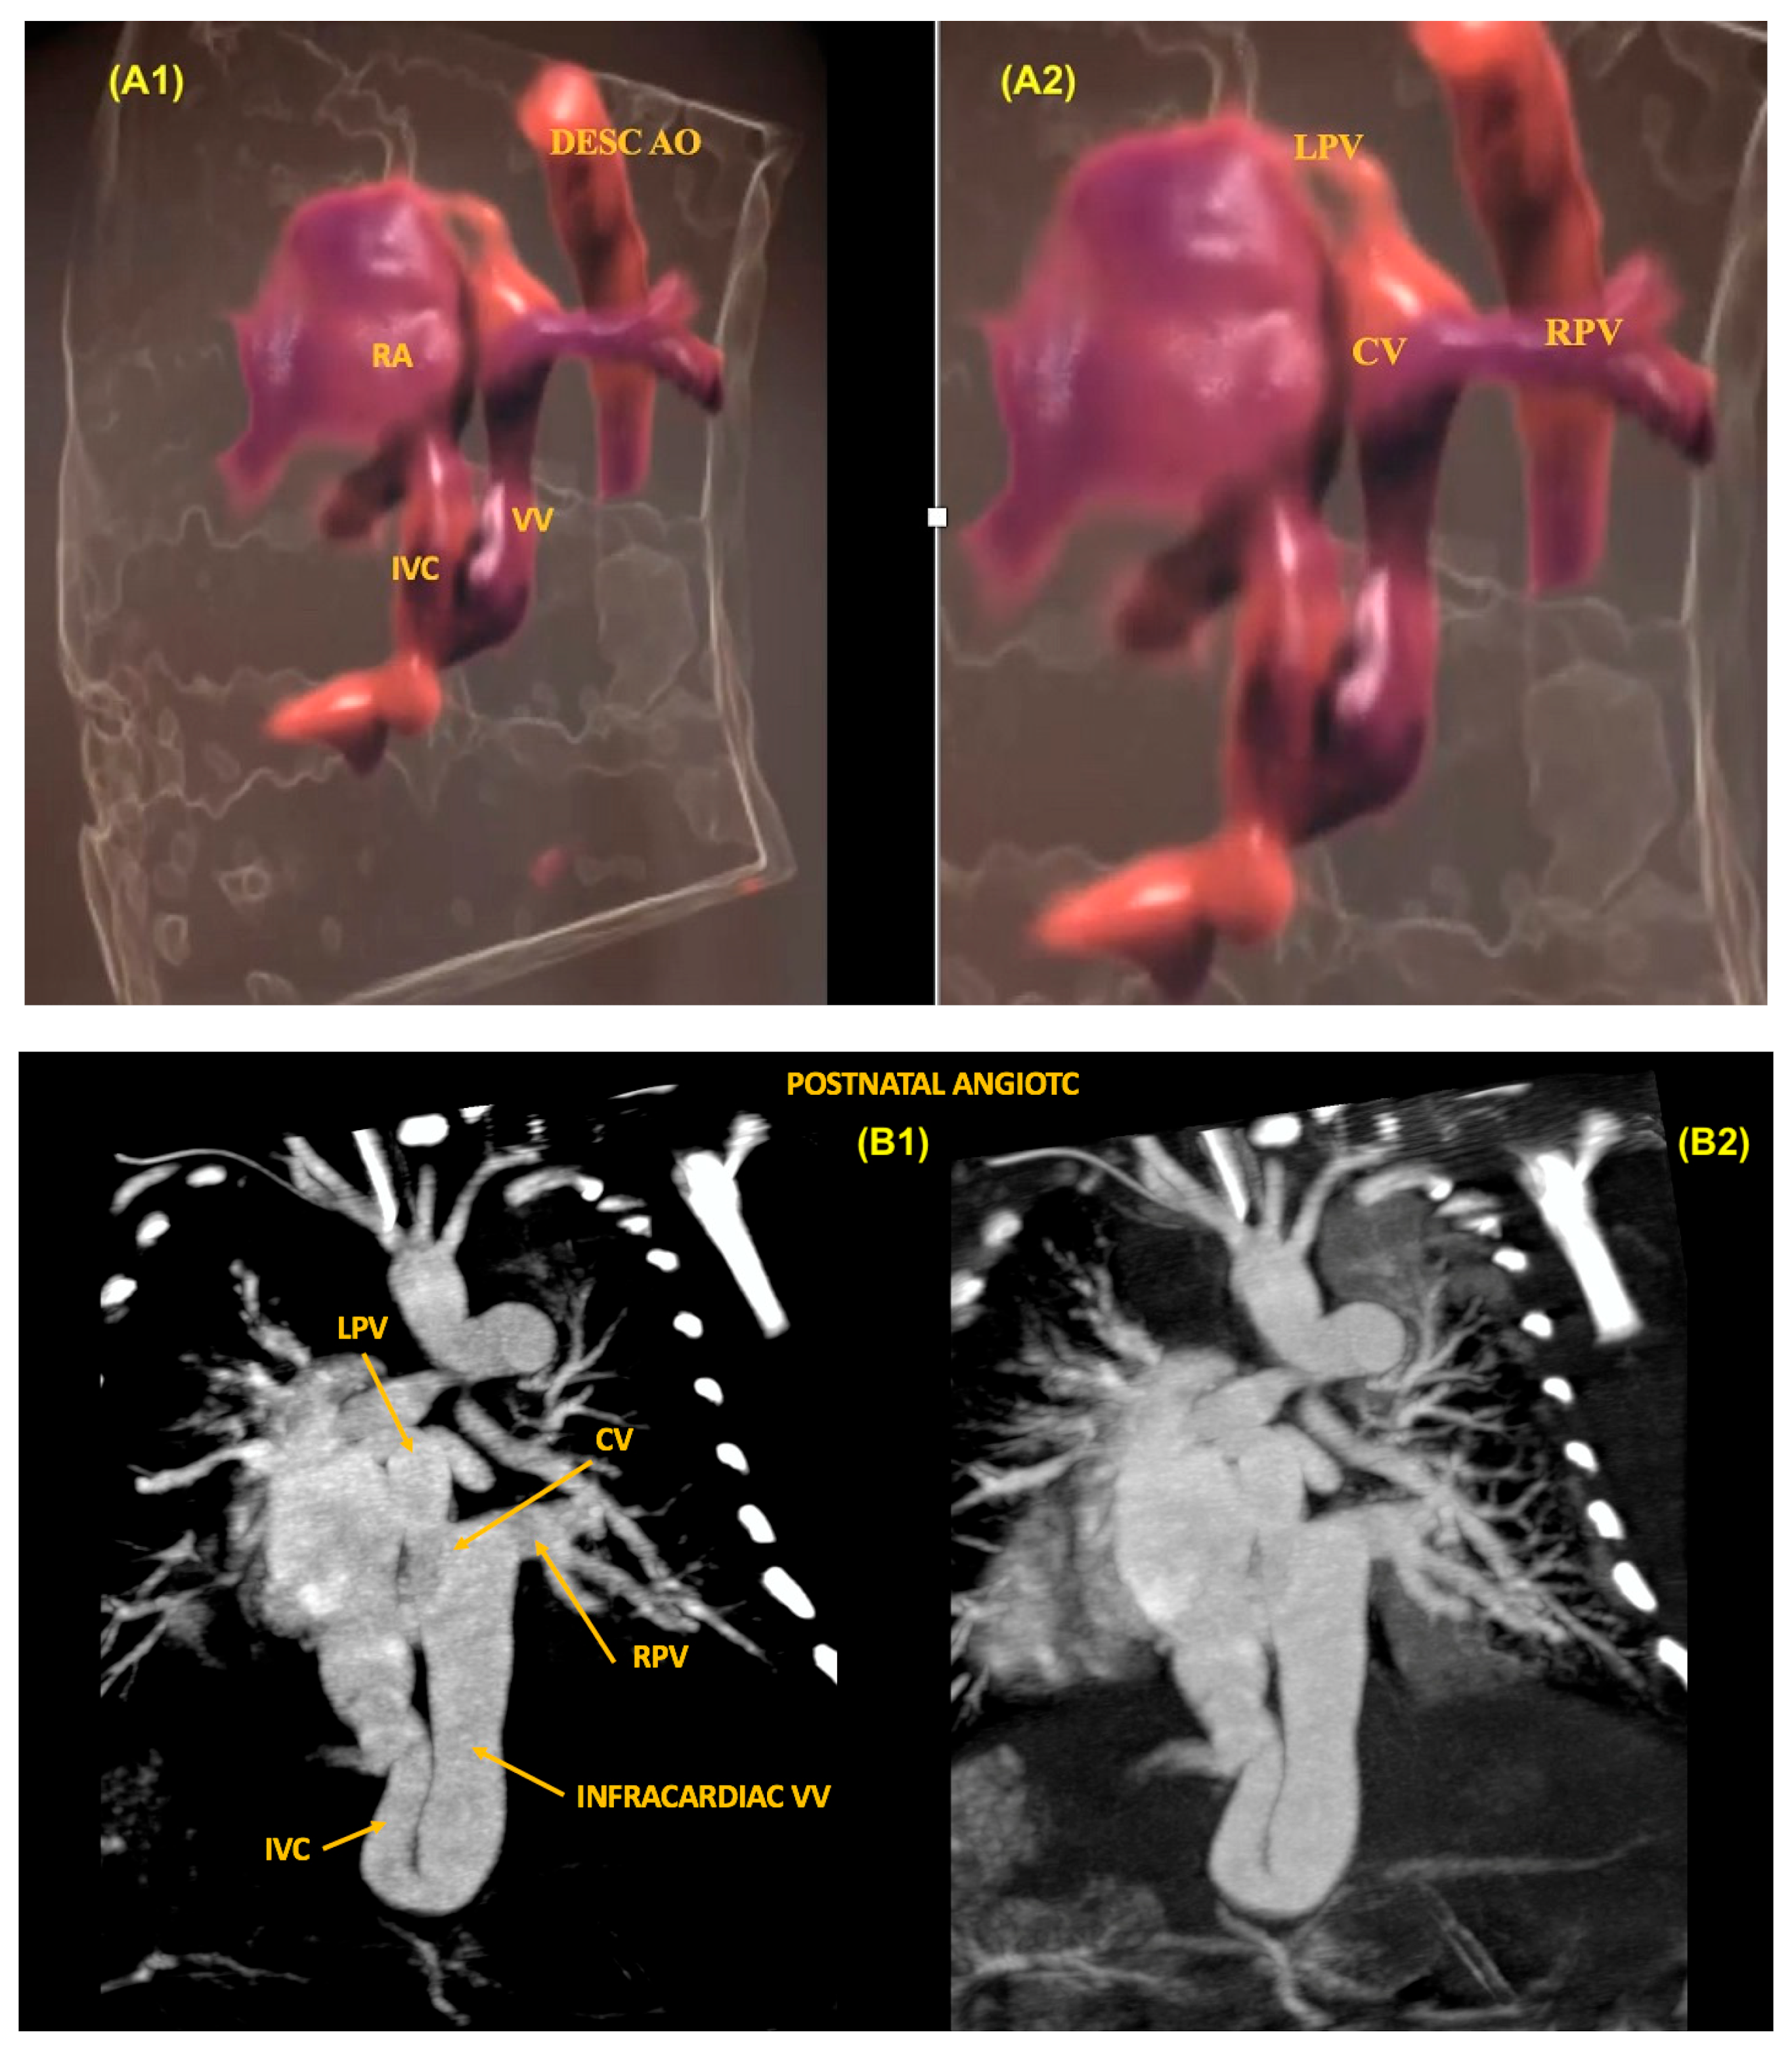

11. Anomalous Venous Return

- Zhang, Y.; Shao, Q.; Sun, L.; Ge, S.; He, Y. Prenatal diagnosis of total anomalous pulmonary venous connection by 2D and 3D fetal echocardiography. Echocardiography 2017, 34, 1852–1857. [Google Scholar] [CrossRef] [PubMed]

- Bravo-Valenzuela, N.J.M.; Peixoto, A.B.; Júnior, E.A. Prenatal diagnosis of total anomalous pulmonary venous connection: 2D and 3D echocardiographic findings. J. Clin. Ultrasound 2021, 49, 240–247. [Google Scholar] [CrossRef]